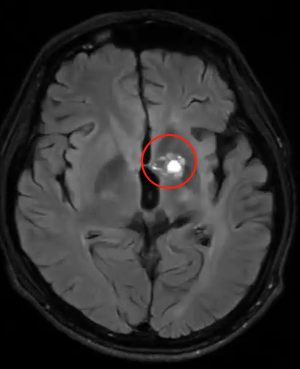

松果体区占位放疗后出现坏死?还有机会安全手术吗?

12岁男孩因面瘫检查发现松果体区占位,约1.8*1.3cm,考虑松果体生殖细胞肿瘤可能,合并梗阻性脑积水。行脑室分流术后症状缓解;后续伽马刀治疗肿瘤缩小至1.0*0.9*1.4cm,但2025年6月复查显示轻微增大(1.2*1.2cm),考虑放疗后坏死可能,仅偶发短暂性头痛。肿瘤究竟是什么类型?尽可能在保留神经功能的前提下,手术可行吗……父母带着各种疑惑找到巴教授。

“手术是可行的,而且预后应该是比较好的,需要关注的就是术后可能会出现短暂的向上凝视麻痹的情况,但是这不是永久的。最终的诊断还是要依据切除肿瘤之后,拿到肿瘤的组织去进行检测。”